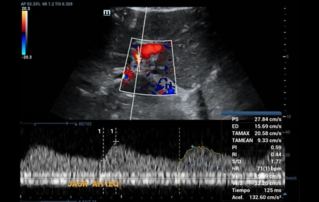

![detection-hypoplastic-left-ventricular-syndrome-second-trimester-screening.thumb.319.319 Ultrasound Journal 36 - Detection of Hypoplastic Left Ventricular Syndrome in Second-Trimester Ultrasound Screening]() Ultrasound Journal 36 - Detection of Hypoplastic Left Ventricular Syndrome in Second-Trimester Ultrasound ScreeningAddressing congenital heart disease: Prenatal ultrasound screening for HLHS enables timely intervention and better patient outcomes. Discover how fetal echocardiography advances the detection and management of this critical condition.Ultrasound Cases | Ultrasound | Smart applications | General imaging 2025-06-19

Ultrasound Journal 36 - Detection of Hypoplastic Left Ventricular Syndrome in Second-Trimester Ultrasound ScreeningAddressing congenital heart disease: Prenatal ultrasound screening for HLHS enables timely intervention and better patient outcomes. Discover how fetal echocardiography advances the detection and management of this critical condition.Ultrasound Cases | Ultrasound | Smart applications | General imaging 2025-06-19 -